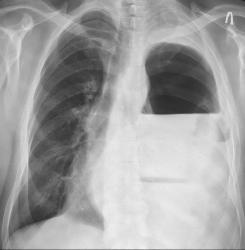

А вот R-контроль после операции:

Окончательно после проведения оперативного вмешательства, диагоноз звучал так : Ущемленная рецидивная грыжа левого купола диафрагмы, некроз желудка, поперечноободочной кишки.